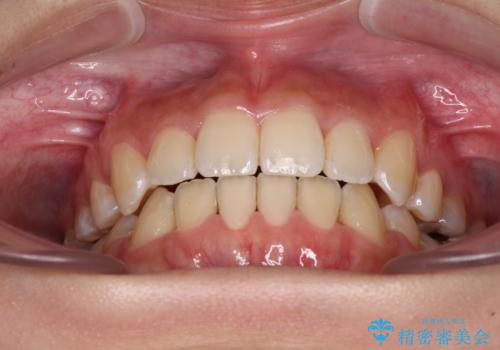

奥歯の咬み合わせが理想的であり、歯の移動に時間のかかる出っ歯でもなかったため、2年程度で治療を終えることを目標としましたが、無事に予定通りの2年間で終えることができました。

- 上下前歯のデコボコと八重歯を気にして来院された患者様です。

叢生を解消する際に出っ歯とならないようにするために、上下左右の小臼歯計4本を抜歯することとしました。